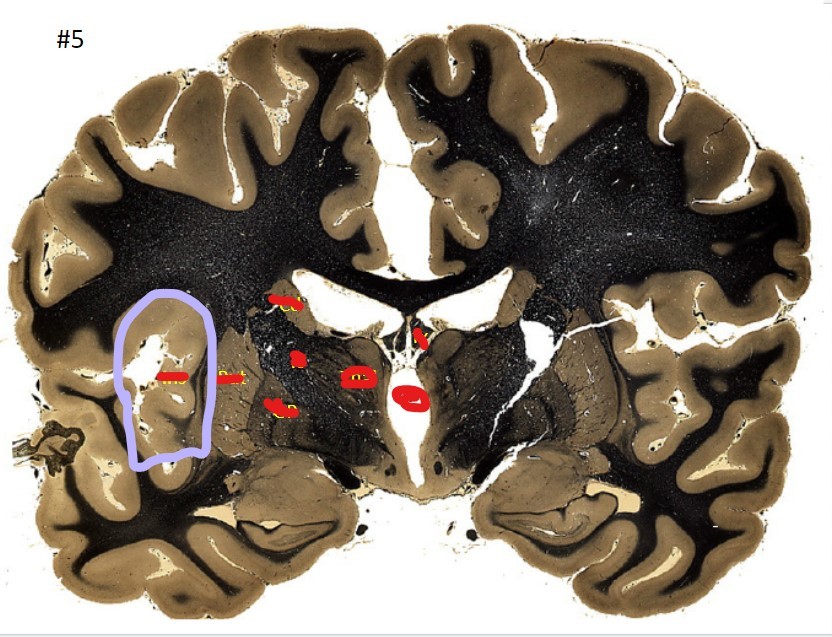

Q

what is the circled area (#5)?

A

the caudate nucleus

21

the 3rd ventricle

22

23

the globus pallidus

24

25

the internal capsule

26

the putamen

27

the amygdala

28

the beginning of the hippocampus